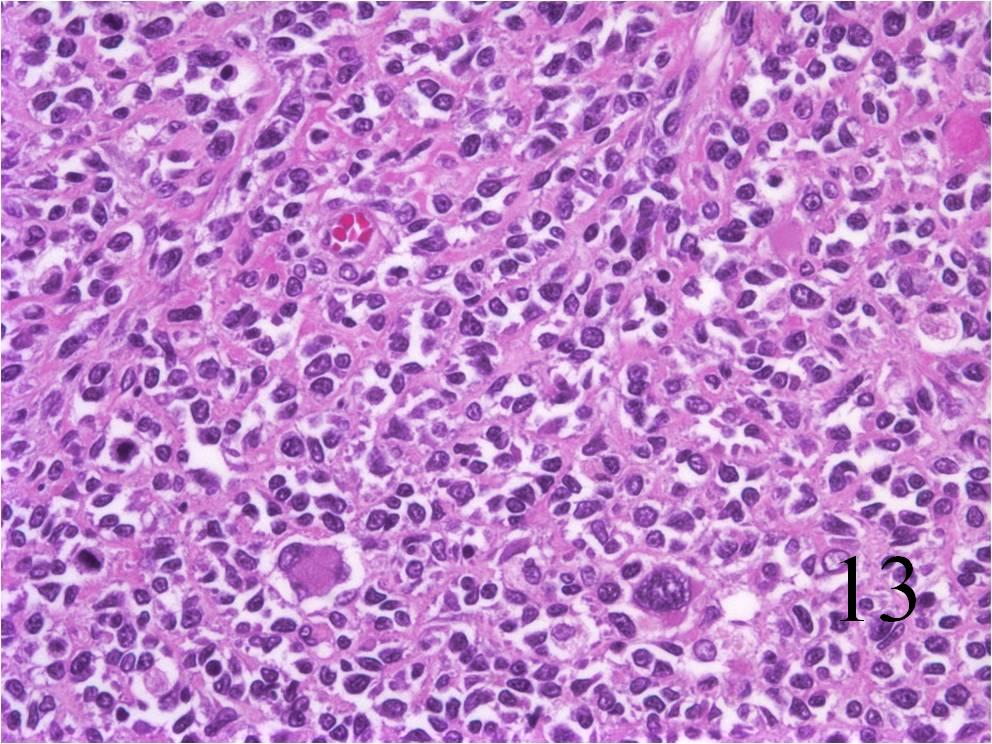

rhabdomyosarcoma alveolar power pathology low cells sarcoma tumor magnification fig abundant small high

Soft Tissue Sarcoma - Pathology - Orthobullets

www.orthobullets.com

www.orthobullets.com

rhabdomyosarcoma pathology orthobullets sarcoma tissue soft bone cell 51c topic donnell patrick

Rhabdomyosarcoma - Pathology - Orthobullets

www.orthobullets.com

www.orthobullets.com

rhabdomyosarcoma orthobullets mri pathology 51a donnell patrick topic